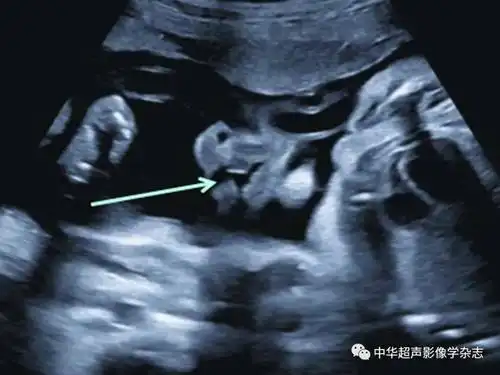

(箭头所示);b:正常胎儿面部正中矢状面下唇裂非常罕见且超声诊断困难

在妊娠20~24周超声检查时,应通过观察鼻唇冠状面判断上唇是否有唇裂